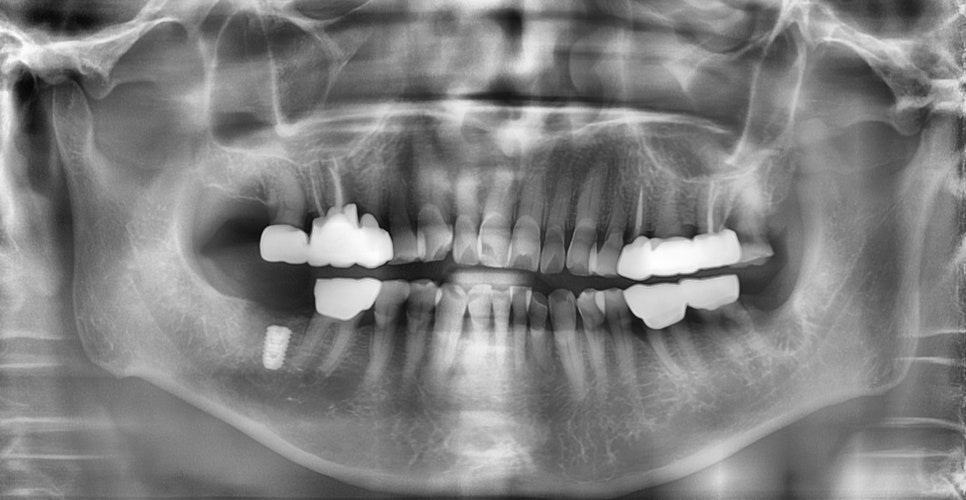

임플란트 픽스쳐 식립

한달 후 임플란트를 식립하였으며, 수술 후 특별히 불편한 사항은 없었다고 하셨습니다. 3달 후 임플란트 보철물을 장착하였습니다.